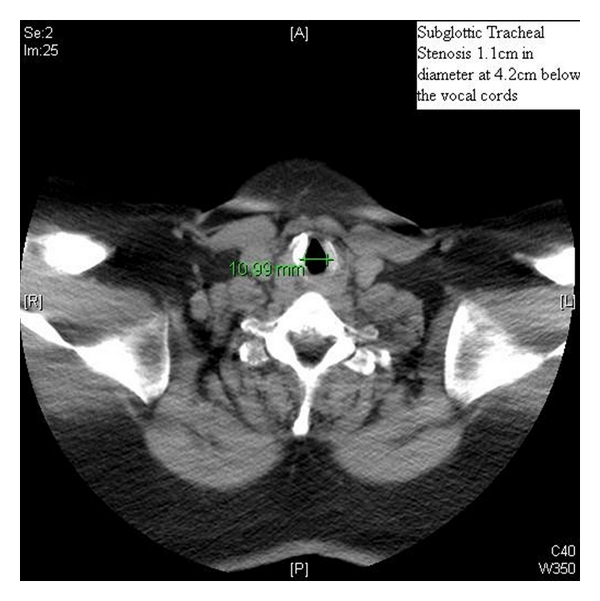

A 45-year-old woman with a long history of tracheal stenosis and upper airway obstruction presented for elective tracheostomy placement in the setting of supra- and infraglottic stenosis after failed awake tracheostomy by an otorhinolaryngologist (ORL) (Figures 1 and 2). It was felt by the attending ORL surgeon that the airway could not be secured from above after serial diagnostic scopes. Due to the failed awake tracheostomy, it was felt that surgical airway under bypass was the only option.